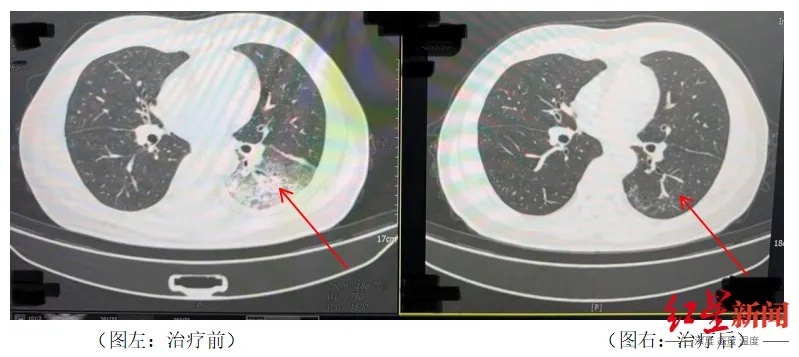

家人见状,当即将他送医。胸部CT显现李先生的。左肺已呈现大面积白色印象,简直占有一半肺部。经过检测,终究确认是。嗜肺军团菌肺炎。

李先生肺部医治前与医治后的比照。